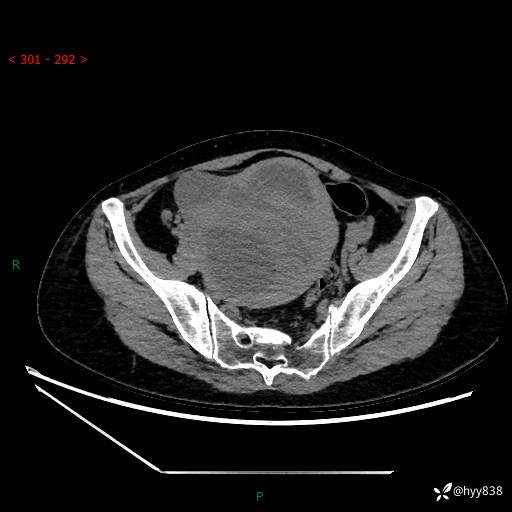

辅助检查:CT

增强(动脉期+静脉期)